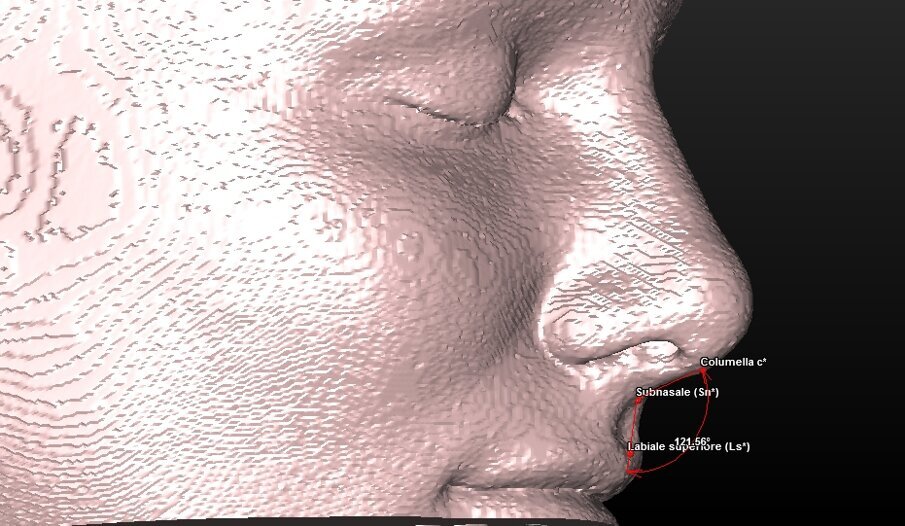

5 landmark per la valutazione estetica dei tessuti molli (Tab. 2) (Fig. 4).

| Sn (Subnasale) |

Punto mediano cutaneo d’incontro tra columella e labbro superiore. |

| Columella |

Punto mediano cutaneo più alto di columella a livello d’incontro tra le narici. |

Componente tessuto molle (Tab. 5) (Figg. 10a-11):

| Angolo Naso-Labiale |

Angolo tra i punti Columella-Subnasale-Labiale superiore |

ig. 4_Ricostruzione 3D dei tessuti molli del paziente con visione dei landmark utilizzati.

Fig. 10a_Valutazione dei tessuti molli: angolo naso-labiale.